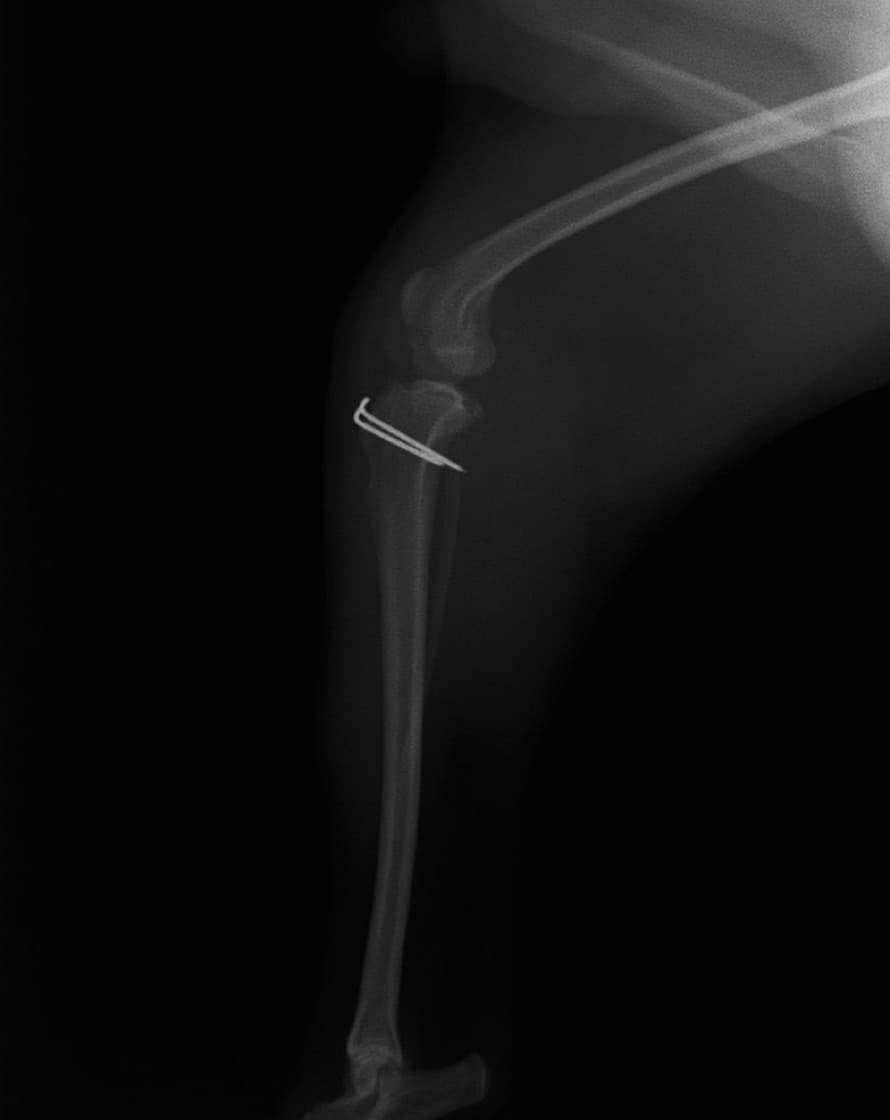

■ 症例20 ポメラニアン 8ヶ月 1.8kg

左右膝蓋骨脱臼 グレードⅢ

2ヶ月前から間欠的跛行が認められ、両膝の膝蓋骨脱臼整復術を行った。

手技は縫工筋及び内側広筋の解放、脛骨粗面の外側転位、滑車ブロック形造溝術、内外側関節包の縫縮を選択し実施した。

右側の膝蓋骨脱臼は上記手技で整復されたものの、左側はそれのみでは膝蓋骨が浮く様子が認められた。その為、PDS縫合糸にて膝蓋靱帯を1糸のみ縫合し、靱帯の縫縮を行った。

膝蓋骨脱臼は膝関節における膝蓋骨の内外側の脱臼と定義されるが、時として単純な内外の脱臼ではなく、膝蓋骨が大きく前方に浮き上がるように脱臼する場合がある。特にトイプードルやポメラニアンといった犬種に多く認められる。

内側脱臼に加えて前方への浮き上がりを矯正する為に、従来より脛骨粗面転移により膝蓋靭帯を外方と下方に引っ張り、固定する方法を選択する。膝蓋骨の前方への浮き上がりが軽度の場合は、従来法ではなく関節包の縫縮で対応していた。しかし、一部の症例で膝蓋骨の動きが悪くなり伸展機構が円滑に機能せずロボット様歩行になるケースがあった。

その為、膝蓋靭帯自体を縫縮する方法を採用した。この方法により、膝関節の伸展機構を妨げず膝蓋骨の軽度の浮きを矯正することが可能となった。

本症例の経過は良好である